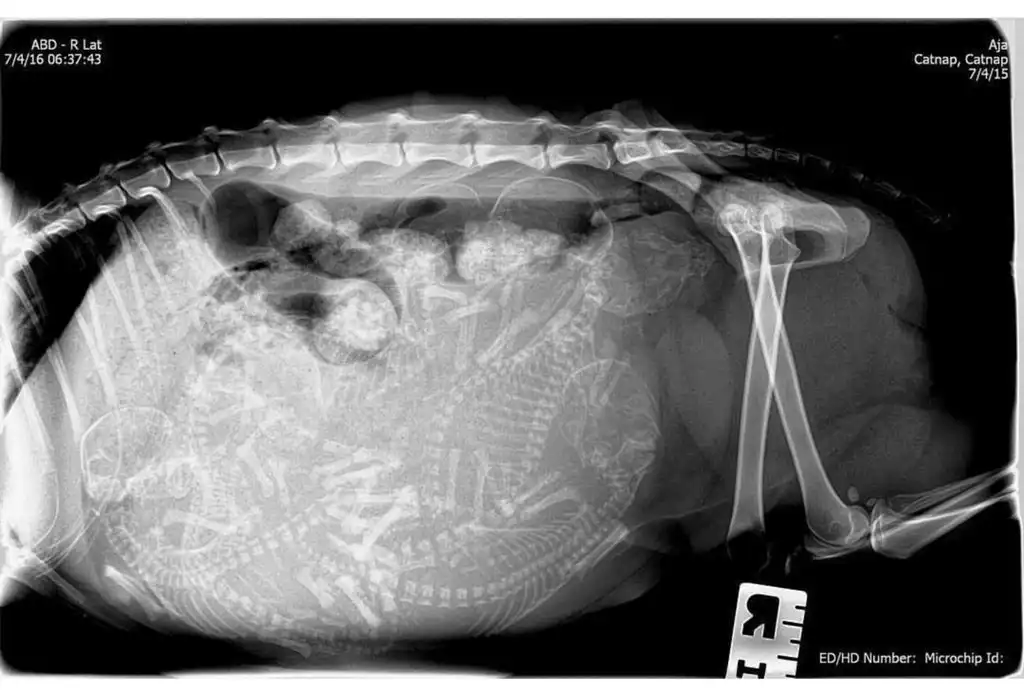

Еще одна беременная котейка